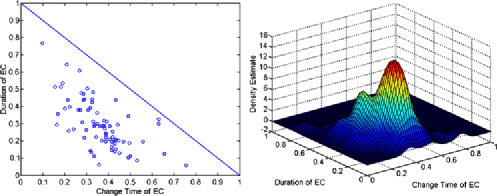

The left panel in Figure 11 shows the estimated change and durations for all those subjects where the null hypothesis of no change was rejected using FDR, while the right panel shows a kernel smoothed density estimate for the joint distribution of position and duration of the epidemic change, using the automatic bandwidth selection procedure of Botev, Grotowski and Kroese (2010) (yielding bandwidths of and ). In this example change-points usually occur somewhere between 0.25 and 0.5, and last around 0.1–0.3 of the scanning period except for very early changes which often last longer. In fact, the density seems to be bimodal, indicating two clusters dividing subjects into those for which a change occurs after a relatively short period in the scanner (maybe only now arriving in the stationary state) in addition to a relatively long duration (possibly until the end of the scan), and those subjects for which after a short time in the epidemic state a return to baseline happens. However, for subjects with a relatively late change, a long duration cannot happen due to the limited time in the scanner. Therefore, the two modes may be an artifact of the statistical procedure based on the short time span.

The results of the study show that resting state scans in some cases do show evidence of deviation from stationarity which can be modeled by epidemic mean changes, at least as a first approximation, indicating that the overall activity is different at different times. This result has implications for studying correlations within the brain between regions of interest using multiple subjects, particularly if some subjects show nonstationary behavior, while others do not.